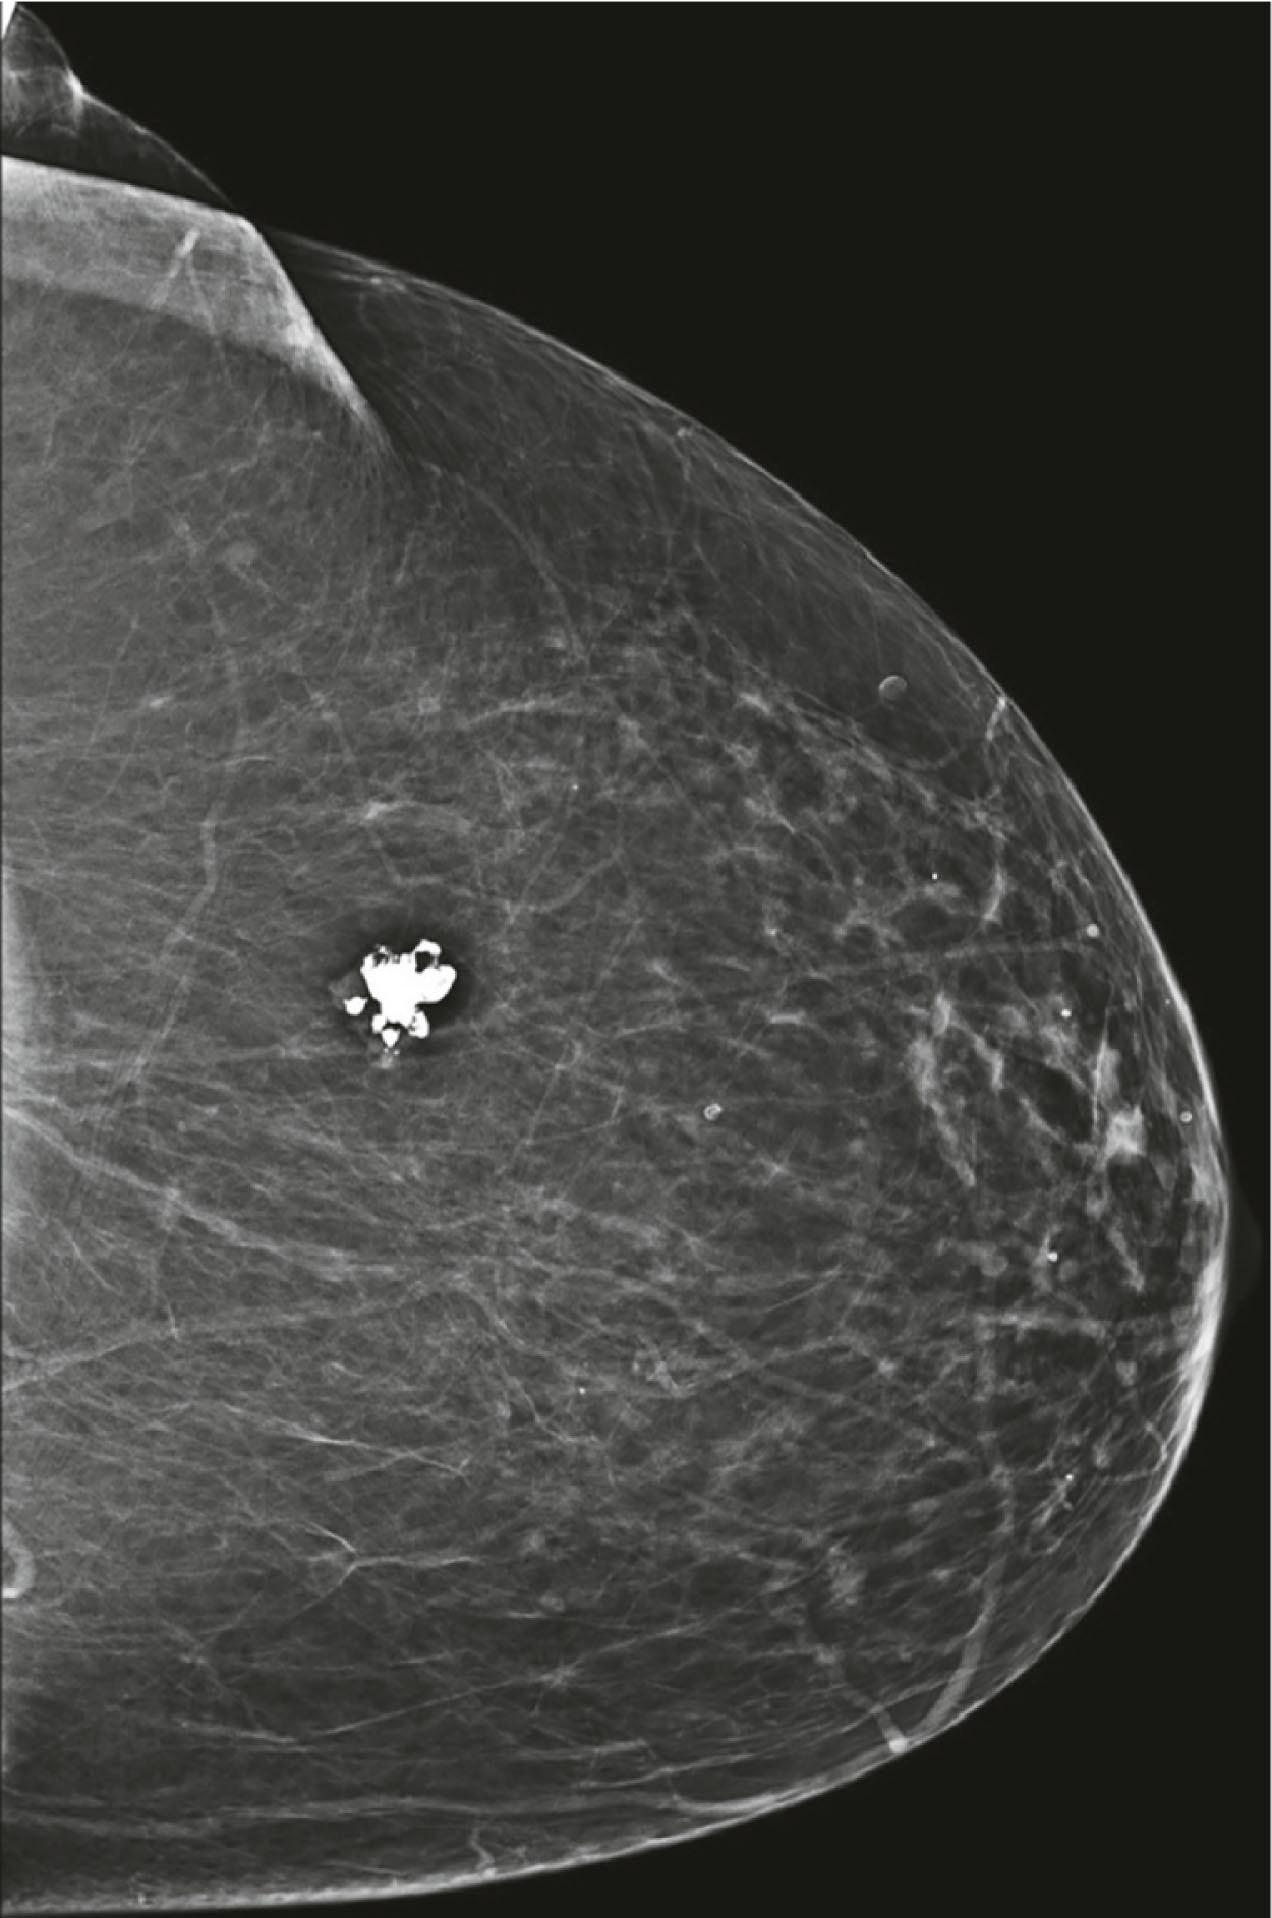

Fibroadenomas are also round or oval, with sharp borders. Unlike cysts, fibroadenomas are solid benign tumors, and sometimes a core biopsy is necessary to establish the diagnosis. Coarse, “popcorn-like” calcifications on mammography are typical of mature fibroademonas ( Fig. 12.7 ).

Fig. 12.7, Coarse, “popcorn-like” calcifications typical of a mature fibroademona.